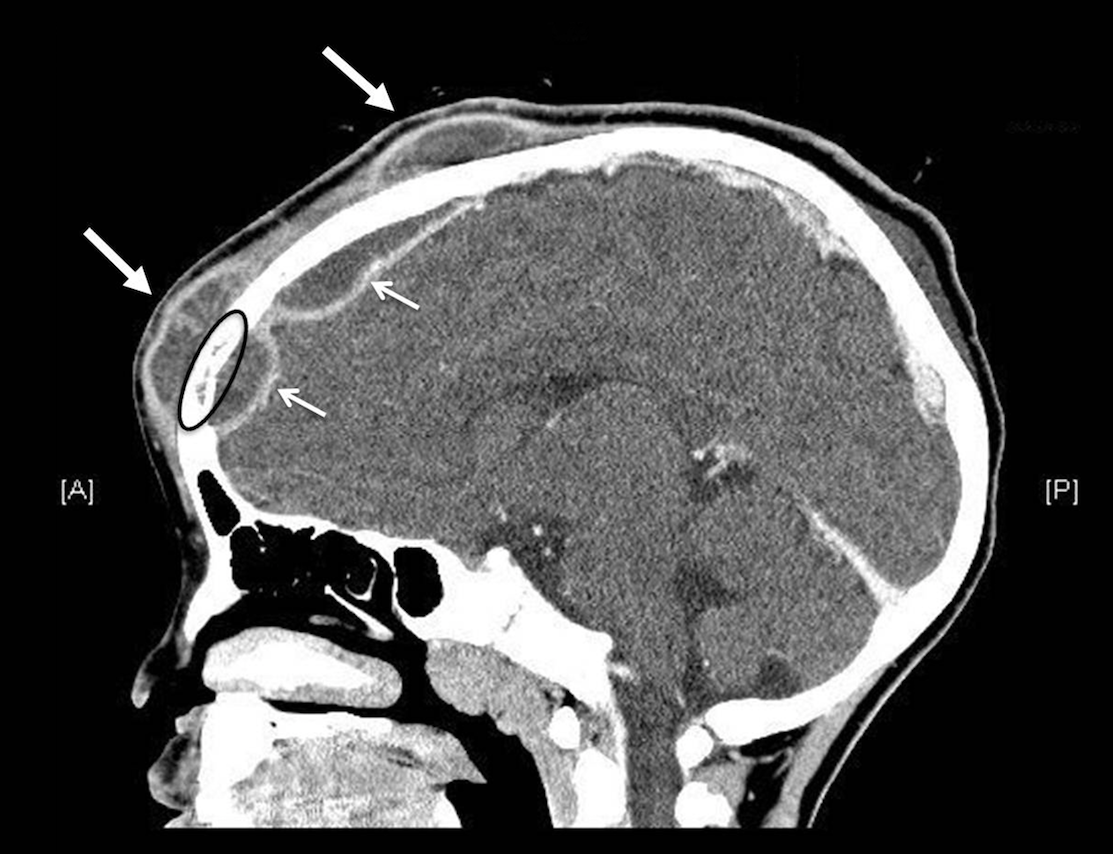

Contributor: Alec Coston, MD Case Report Summary: A 17-year-old female involved in a motor vehicle collision presented to a rural emergency facility via personally operated vehicle. During workup and initial CT scan, the patient began rapidly decompensating with CT revealing a 1.5cm epidural hematoma with 7mm of midline shift. The patient went from being able to walk and talk to being obtunded with a blown left pupil and unresponsive. Following intubation, the patient was being prepared for transport but potential delays required immediate emergency evacuation of the hematoma via a Burr Hole. A traditional Burr Drill was not immediately available at the facility, so an improvised Burr Drill using an Intraosseous (IO) drill was used. 35mL of blood was removed from the hematoma and the patient immediately improved from a GCS of 3 to GCS of 8. The patient was transferred to a higher level of care facility, extubated the following day, and made a full neurological recovery. Educational Pearls: What is an epidural hematoma? An epidural hematoma is a collection of blood between the dura mater (outermost layer of the meninges) and the skull, whereas a subdural hematoma is a collection of blood between the dura mater and arachnoid mater. Both can be life threatening depending on location and size. Epidural hematomas tend to be arterial, and are typically secondary to trauma and can rapidly expand, but with timely recognition and evacuation of the bleed, favorable outcomes are often possible. What are typical intracranial pressures and at what levels do they become pathologic? Typical intracranial pressure (ICP) varies by age, but past infancy and early childhood, adolescents and adults have a value typically between 8-15mmHg. Values exceeding 20mmHg become pathologic and rise exponentially with increased volume. Initial symptoms may include headache, nausea, and vomiting, but with increased pressures may progress to more life threatening symptoms such as loss of consciousness, cranial nerve palsies, pupillary constriction or dilation (sign of herniation), and respiratory irregularities. What is the takeaway in timing of epidural hematomas? Older studies show that evacuation of a hematoma with lateralizing features before the two hour mark of coma symptom onset is correlated with decreased mortality (ranging from 15-17%), but beyond 2 hours the mortality increases to well over 50%. Though mortality statistics have grown more variable, early targeted evacuation of epidural hematomas still remains critical for improved patient outcomes. In austere conditions with limited resources, improvisation with interosseous drills and needles can improve patient outcomes and achieve the target therapy for epidural hematomas. References Haselsberger K, Pucher R, Auer LM. Prognosis after acute subdural or epidural haemorrhage. Acta Neurochir (Wien). 1988;90(3-4):111-116. doi:10.1007/BF01560563 Hawryluk GWJ, Nielson JL, Huie JR, et al. Analysis of Normal High-Frequency Intracranial Pressure Values and Treatment Threshold in Neurocritical Care Patients: Insights into Normal Values and a Potential Treatment Threshold. JAMA Neurol. 2020;77(9):1150-1158. doi:10.1001/jamaneurol.2020.1310 Pisică D, Volovici V, Yue JK, et al. Clinical and Imaging Characteristics, Care Pathways, and Outcomes of Traumatic Epidural Hematomas: A Collaborative European NeuroTrauma Effectiveness Research in Traumatic Brain Injury Study. Neurosurgery. 2024;95(5):986-999. doi:10.1227/neu.0000000000002982 Summarized by Dan Orbidan, OMS2 | Edited by Dan Orbidan and Jorge Chalit, OMS4 Donate: https://emergencymedicalminute.org/donate/